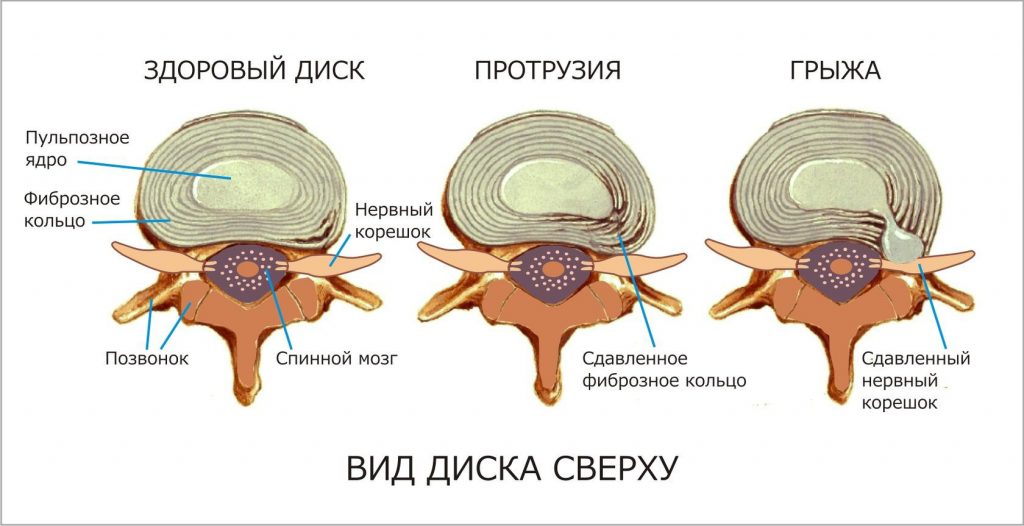

КТ-протрузии дисков: Визуализация и классификация